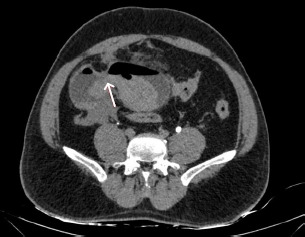

Abstract Image